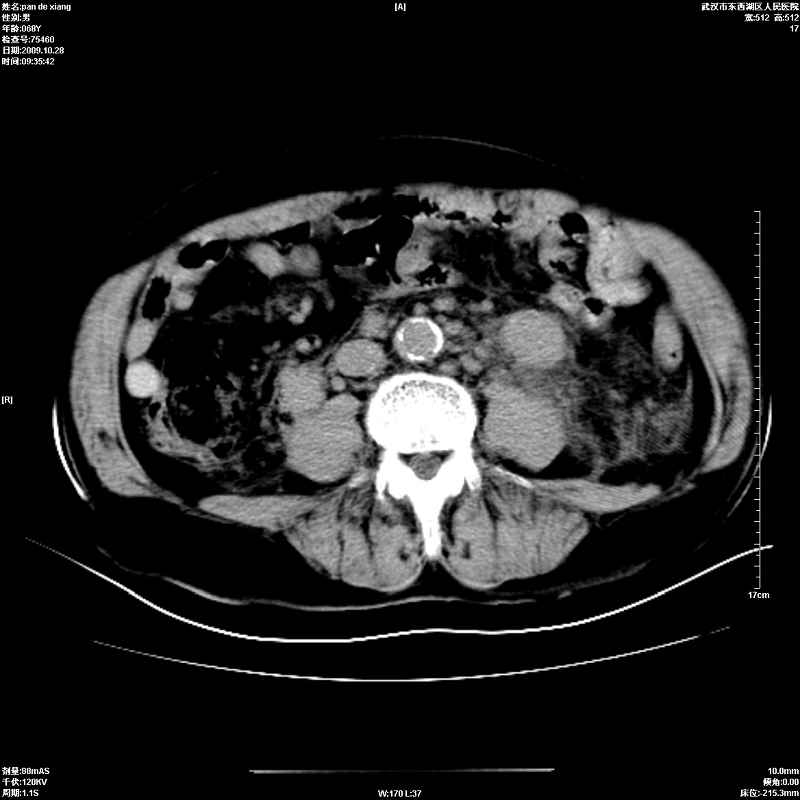

以下是引用杀毒软件在2009-10-28 20:41:00的发言:[br]结合临床考虑---白血病双肾改变或淋巴瘤。

以下是引用zxl51642在2009-10-29 9:59:00的发言:[br]结合临床“单克隆免疫球蛋白血症”,考虑双肾为继发损害并肾功能不全(尿中大量igg及少量iga、igm等大分子免疫球蛋白滤出所致继发损害),椎前软组织肿块为髓外造血。与浆细胞瘤有区别,平扫时有战友说的很清楚。